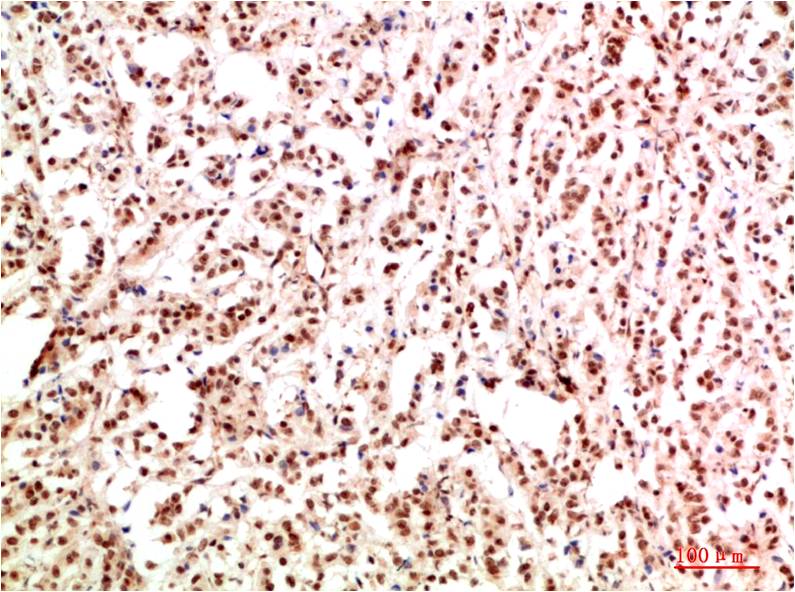

STAT1 Rabbit Polyclonal Antibody

Catalog NO.:BE3403

Applications :WB, IHC

Reactivity :H,R,M

STAT1 is a member of the Signal Transducers and Activators of Transcription family of transcription factors. STAT1 is involved in upregulating genes due to a signal by either type I, type II, or type III interferons

| Recommended dilutions: | WB:1:1,000-2,000 IHC:1:200-500 |

| Specificity: | Antibody can detects endogenous STAT1 protein. |